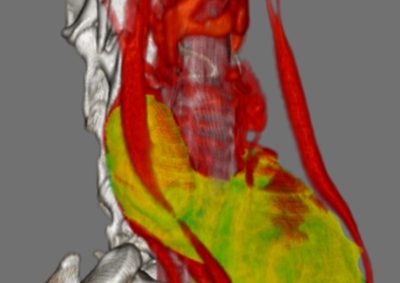

腫瘍外科 注意 ボタンをクリックした先に、治療中および手術中の画像が説明で使用されている場合がございます。 そのような画像に弱い方は閲覧なさらないようお願いいたします。 腫瘍外科 フレンチブルドッグ胃腺癌 胃部分切除 軟部組織外科腫瘍外科救急・集… 肝臓腫瘤破裂による腹腔内出血 腫瘍外科腫瘍内科 猫の直腸切除吻合 直腸リンパ腫 腫瘍外科 犬の肺腺癌の1例 腫瘍外科放射線治療 犬の軟部組織肉腫に対する腫瘍辺縁切除及び術後放射線療法 腫瘍外科 犬の肝細胞癌 軟部組織外科腫瘍外科 ジャックラッセルテリアの胃腫瘍 腫瘍外科 吻側下顎骨切除術〜メラノーマ〜 腫瘍外科 猫の上顎腫瘍切除 腫瘍外科 犬の脾臓腫瘤摘出 軟部組織外科腫瘍外科 大腸腺癌 軟部組織外科腫瘍外科 肺葉切除術 <1234567> 症例カテゴリー 放射線治療整形外科軟部組織外科脳神経外科内科腫瘍外科救急・集中治療リハビリテーション科腫瘍内科内視鏡科脳神経科呼吸器外科中医・漢方猫の腎移植循環器科